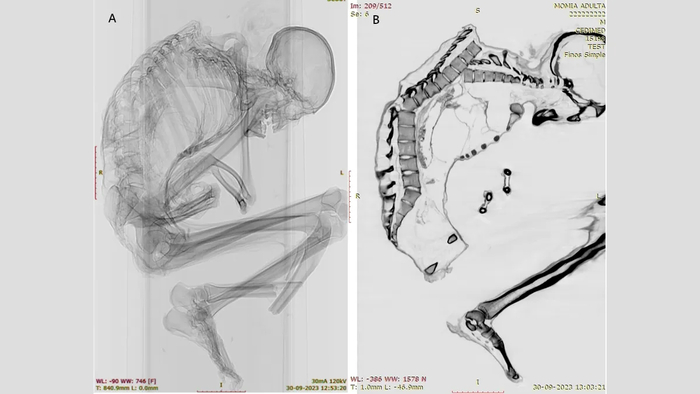

Поэтому крайне редкой удачей можно назвать находку KNM-ER 101000 – частичного скелета, включающего зубы и фрагменты черепа, кости рук и ног. Его нашли в Кении, в местонахождении Кооби Фора, на восточном берегу озера Туркана в 2019 году и в течение 2 лет по частям извлекали из окаменевшего песчаного ила. Скелет, кстати, находился прямо над древней поверхностью, на которой нашли цепочку следов, предположительно, парантропа вместе с двумя следами кого-то очень похожего на Homo. Возраст найденных костей чуть больше 1,52 млн лет.

Строение и огромные размеры зубов KNM-ER 101000 позволяют однозначно отнести эту находку к парантропам. Части черепа тоже явно парантропьи, в том числе теменной фрагмент, на котором виден мощный выступающий гребень – именно такие украшали черепа самцов P. boisei.

Вместе с набором зубов ученые нашли много костей правой и левой рук, причем кости не дублируются и все сходного размера – так что, вероятно, принадлежали одной особи. В том числе, найдены 9 фаланг, включая фаланги большого пальца, и несколько пястных костей.

Что же можно сказать про кисть парантропа Бойса? Судя по всему, её пропорции были вполне как у человека, в том числе имелся достаточно длинный большой палец. У современных человекообразных обезьян большой палец короткий относительно остальных длинных и изогнутых пальцев, отлично приспособленных для хватания за ветки. У парантропа же большой палец длиннее указательного. По мнению ученых, кисть парантропа была вполне способна противопоставлять большой палец остальным и осуществлять точечный захват – свойство, важное при тонких манипуляциях, в том числе при изготовлении орудий. Пальцы, судя по всему, были хорошо подвижными.

Однако некоторые особенности кисти отличаются от человеческих, например у парантропа был очень массивный мизинец, что скорее сближает его с гориллами. По-видимому, так называемый «щипковый» хват такой кистью было не сделать. В целом все пальцы массивны, а конфигурация лучезапястного сустава, видимо, была примитивной. В то же время фаланги пальцев не так сильно изогнуты, как у шимпанзе и горилл, то есть парантроп вряд ли постоянно лазил по деревьям. «Промежуточная фаланга KNM-ER 101000 является одной из наименее изогнутых среди ископаемых образцов», - говорится в статье.

Судя по сохранившемуся фрагменту левой лучевой кости, парантроп был обладателем мощных бицепсов. На могучие руки этих человекообразных указывают и другие находки.

А еще скелет включает несколько костей правой стопы, и судя по их строению стопа парантропа была жёсткой, неспособной к захвату, но приспособленной к двуногому хождению. В то же время, большой палец стопы короче, чем у человека, и видимо механика походки несколько отличалась от нашей.

Части посткраниального скелета KNM-ER 101000: кисти, фрагмент лучевой кости (справа вверху) и стопы (справа внизу)

Итак, парантроп с такими руками вполне мог заниматься орудийной деятельностью, хотя, вероятно, свои мощные руки использовал не совсем так, как мы. Мощные руки позволяли бы парантропу Бойса лазить по деревьям, однако стопа скорее говорит о наземном образе жизни.